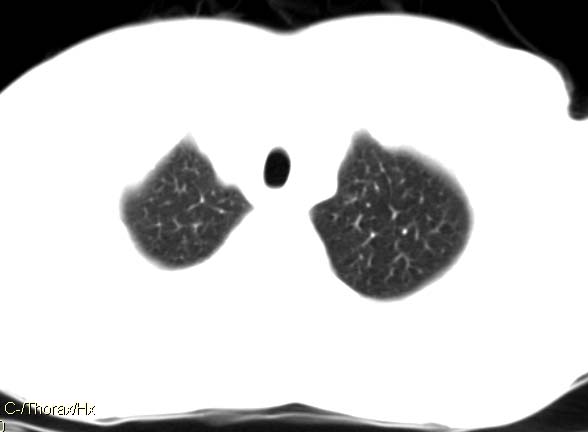

以下是引用qingyuan在2007-4-17 14:19:00的发言:[br]右肺下叶外侧后段胸膜下区节结样病变、分叶、内可见空洞,壁厚薄不均,胸膜凹陷、肺门周围区纹理增粗、僵硬、并近似小结节样改变,肺门区软组织节结、纵膈淋巴结肿大,患者病史长、抗炎治疗无好转炎性改变基本排除,考虑:右肺下叶周围型肺癌伴纵膈及右肺门区淋巴结转移、肺内淋巴管受侵。